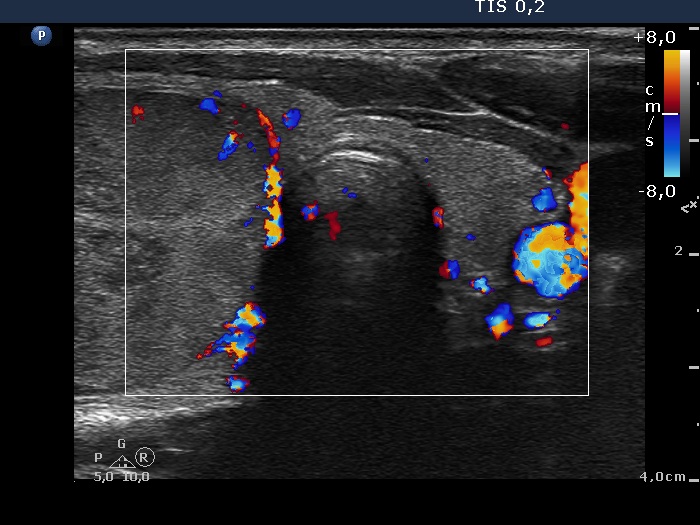

Study on 100 consecutive patients with thyroid nodule - case 031 (ultrasonographic picture 6)

Left lobe, transverse scan, color Doppler mode. The left lobe presents non-specific vascularization while the perinodular blood flow of the nodule in the right lobe can be seen well.